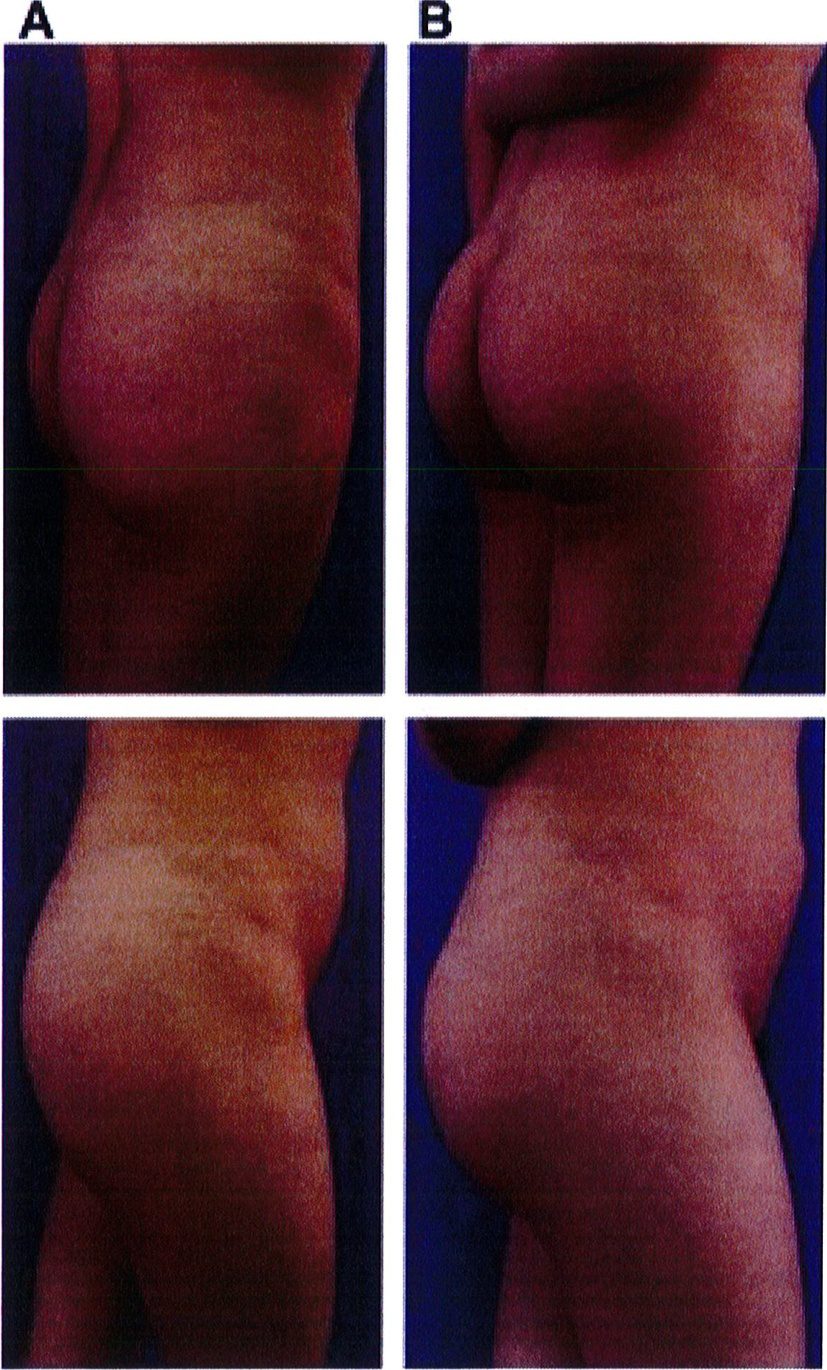

Hình. 21. (A) Hình anh trước và (B) và sau phẫu thuật làm đầy mông của bệnh nhân có vùng thắt lưng tương đối phẳng. Bệnh nhân được đặt khối im- plant dưới cân thế tích 330 mL ở hai bên.

KẾT QUẢ

Cuối cùng, một bệnh nhân 48 tuổi có vùng thắt lưng tương đối phẳng. Với tiền sử đã từng hút mỡ và hiện tại đang mong muốn được làm đầy mông để cải thiện hình thể phần thắt lưng (một cách tương đối). Hai khối implant mi- crotextured thể tích 300 mL được đặt ở dưới cân. Bệnh nhân được tiếp tục điều trị bằng liệu pháp siêu âm (dùng sóng siêu âm) sau phẫu thuật nhằm giảm phản ứng viêm tại chỗ. Sau phẫu thuật không ghi nhận biến chứng (Hình 21).